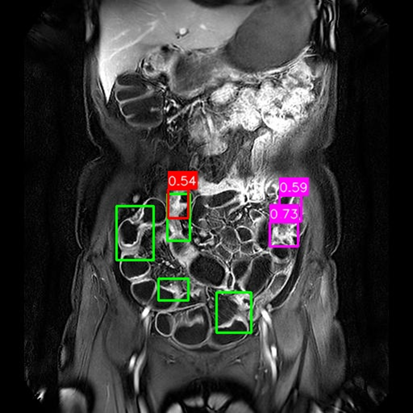

(a) Mask R-CNN [He2017MaskRCNN]

Refer to caption

(b) DiffusionDet [Chen2023DiffusionDet_ICCV]

(c) DeFloMat (Ours)

Figure 3: Qualitative Comparison on Crohn’s Disease MRE Test Set. The figure compares detection results from (a) Mask R-CNN, (b) DiffusionDet (S=3S=3), and (c) DeFloMat (Ours, S=3S=3) on challenging MRE slices. Green boxes indicate True Positives (TP, IoU 0.1\geq 0.1), Red boxes indicate False Positives (FP), and Purple boxes indicate False Negatives (FN). DeFloMat consistently demonstrates superior localization quality and sensitivity: it successfully detects subtle inflammation regions (TP) that are often missed (FN, Purple boxes) by the Mask R-CNN baseline (Row 2, 4). Furthermore, DeFloMat provides tighter bounding box localization compared to DiffusionDet, confirming the benefit of learning the direct, deterministic flow field. The results show DeFloMat’s robustness in capturing varying sizes and numbers of inflammatory lesions.

Qualitative Assessment.

Figure 3 provides visual evidence of the models’ performance on challenging MRE slices, where inflammatory lesions can be subtle or obscured. The qualitative results underscore DeFloMat’s enhanced localization fidelity. In challenging cases (e.g., Row 2 and 4), Mask R-CNN and DiffusionDet frequently produce False Negatives (FN, Purple boxes), failing to detect clear inflammation sites. In contrast, DeFloMat reliably converts these FNs into True Positives (TP, Green boxes) by providing tighter and more accurate bounding box predictions. This suggests that the deterministic velocity field learned via Flow Matching is highly effective at precisely directing the proposal centers towards the true lesion locations, a characteristic that is vital for accurate clinical reporting. DeFloMat’s ability to achieve such precise localization with only S=3S=3 steps highlights its clinical utility for rapid diagnostic auxiliary systems.